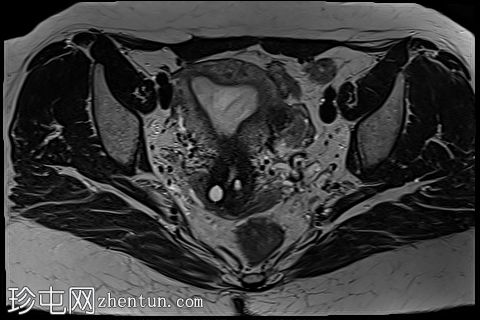

轴位

T2加权像

5.jpg

子宫前壁交界区局灶性增厚,边界不清。形成直径约3厘米的局灶性肿块样病变,轻度压迫膀胱。肿块边界模糊不清,可见多个细小出血灶,在T1加权像和T2加权像上均呈高信号,提示局灶性子宫腺肌症。

子宫体前壁可见另一处病灶,位于上述病灶尾侧,边界清晰(有包膜)。该病灶在T1和T2加权像上均呈低信号,内部未见异常信号灶,周围可见少量明显血管通道,提示为小型子宫肌瘤。

边界模糊不清是局灶性子宫腺肌症(无包膜)的特征。此外,病灶内存在多个微小的内部出血灶(异位腺体),且邻近增厚模糊的交界区,这些都是局灶性子宫腺肌症的诊断标准。

在上述病灶尾侧可见另一处具有不同影像学特征的病灶,该病灶边界清晰(有包膜),且信号均匀(无微小的内部出血灶),提示可能合并子宫肌瘤。